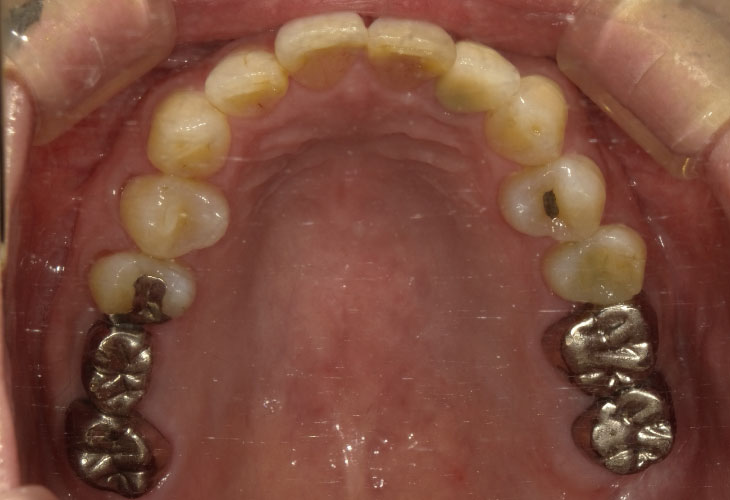

治療内容 インプラント(右下6・7)

オールセラミックス(左上2)

E-MAX CAD(左上6・7)

オールセラミック、E-MAX CAD: 4ヶ月/6回

費用 インプラント: 700,000円

オールセラミック、E-MAX CAD: 269,500円

合計 969,500円